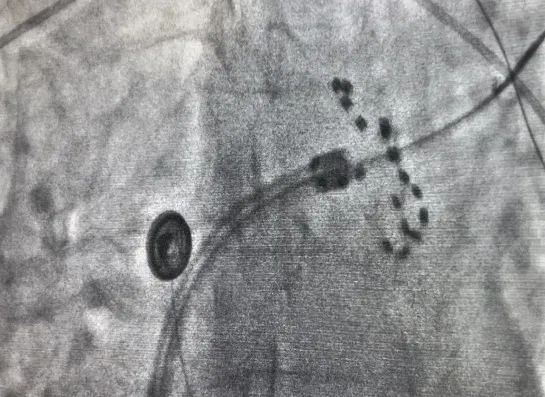

上图为X线下farapulse导管的两种形态:网篮状(左)和花瓣

脉冲消融术后,经验证患者的肺静脉均完成了电隔离。其中第一位患者脉冲消融时长为13分钟;第二位患者脉冲消融时长为25分钟,左心耳封堵时长20分钟,两台手术均高效完成,术后两名患者各项体征正常,安全返回病房,无任何并发症或不良事件。